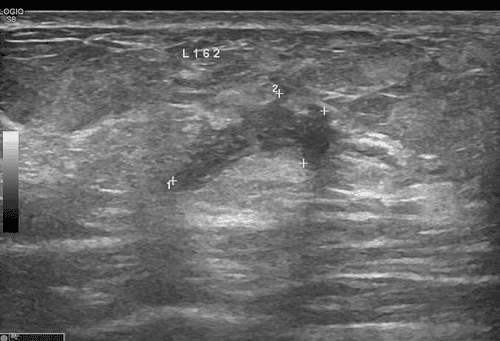

At Vinmec Times City International General Hospital, the patient was examined and found to have severe internal tibial torsion, along with other abnormalities. The deformity had an internal angle of 51.4 degrees in relation to the joint surface, a leg length discrepancy of 4 cm, pelvic tilt, scoliosis, thigh muscle atrophy, and ankle joint involvement, including deformation and degeneration of the ankle joint.

This technique has several advantages over traditional osteotomy methods, especially for cases with severe or very severe deformities. Thanks to the support of 3D printing technology, the surgery was successful.

After calculating the surgical plan on the computer, the patient's bone model was 3D printed for experimental surgery. After the success of the experiment, a personalized 3D-printed surgical guide was used in the surgery, allowing the surgeon to make precise bone cuts as planned, resulting in a smooth, complication-free surgery.

After the surgery, the leg’s axis was restored to be as straight as a healthy leg, and the patient began physical therapy immediately, with a favorable prognosis.